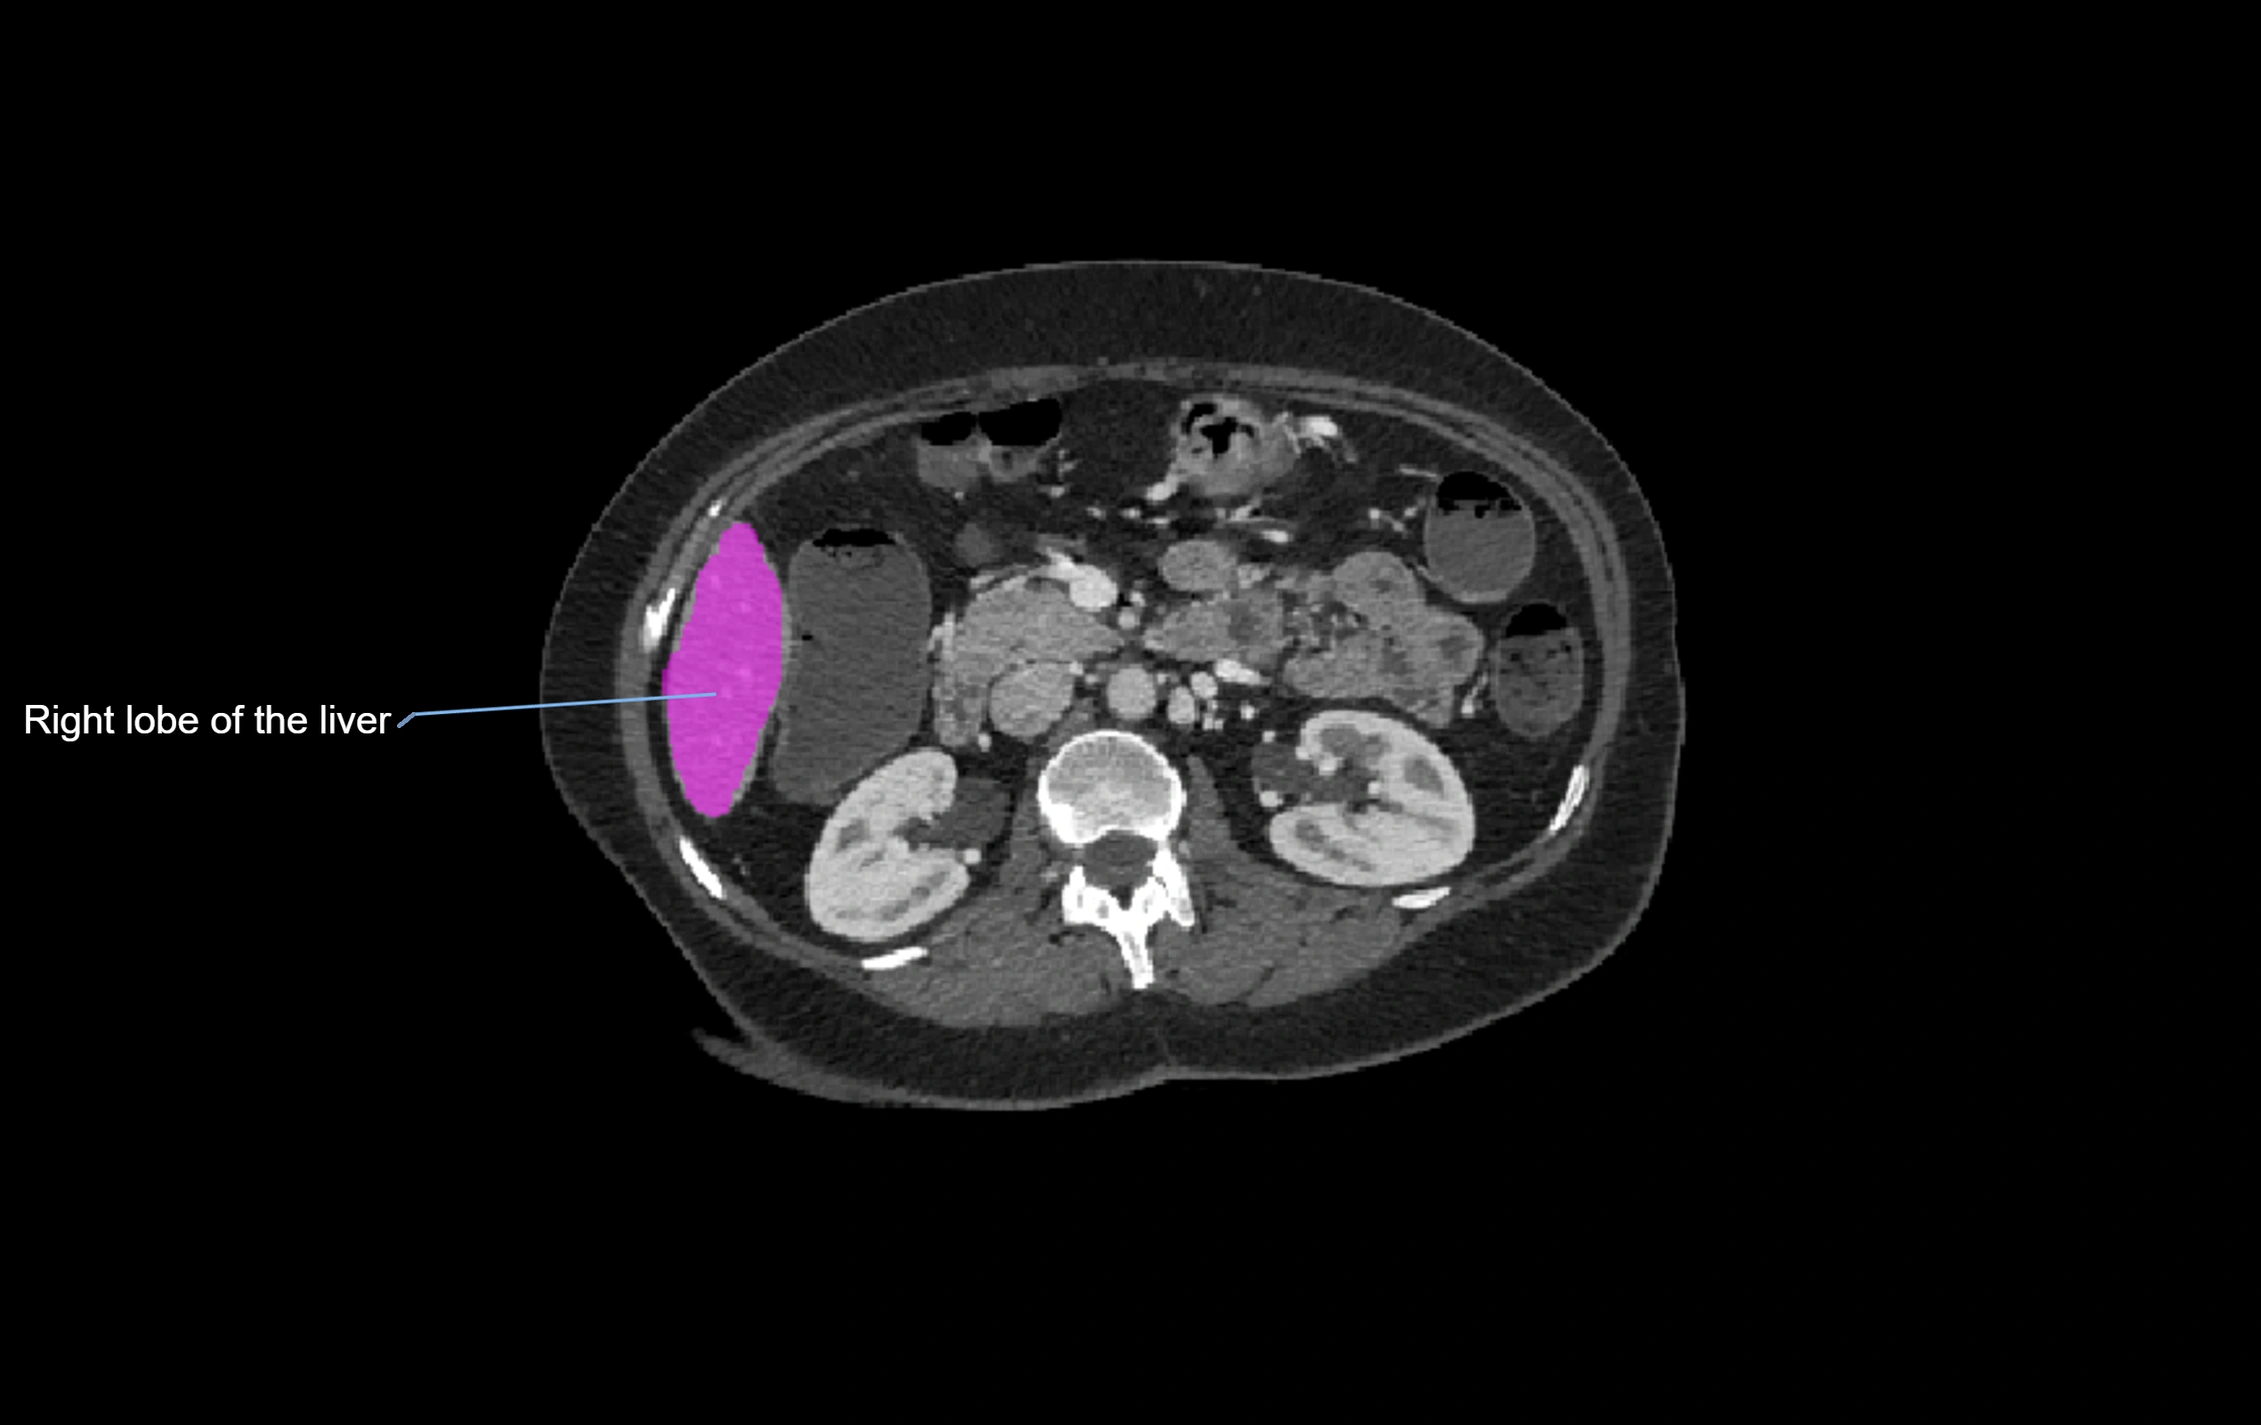

CT Image

image